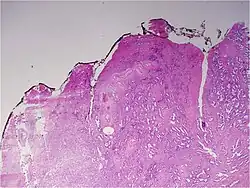

![]() Gleason grade — Lower grades are associated with small, closely packed glands. Cells spread out and lose glandular architecture as grade increases. Gleason score is calculated from grade as described in the text. |

A pathologist microscopically examines the biopsy specimen for certain "Gleason" patterns. These Gleason patterns are associated with the following features:

- Pattern 1 – The cancerous prostate closely resembles normal prostate tissue. The glands are small, well-formed, and closely packed. This corresponds to a well differentiated carcinoma.

- Pattern 2 – The tissue still has well-formed glands, but they are larger and have more tissue between them, implying that the stroma has increased. This also corresponds to a moderately differentiated carcinoma.

- Pattern 3 – The tissue still has recognizable glands, but the cells are darker. At high magnification, some of these cells have left the glands and are beginning to invade the surrounding tissue or having an infiltrative pattern. This corresponds to a moderately differentiated carcinoma.

- Pattern 4 – The tissue has few recognizable glands. Many cells are invading the surrounding tissue in neoplastic clumps. This corresponds to a poorly differentiated carcinoma.

- Pattern 5 – The tissue does not have any or only a few recognizable glands. There are often just sheets of cells throughout the surrounding tissue. This corresponds to an anaplastic carcinoma.

In the present form of the Gleason system, prostate cancer of Gleason patterns 1 and 2 are rarely seen. Gleason pattern 3 is by far the most common.